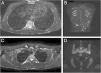

Patient 1: Axial Short Tau Inversion Recovery (STIR) MRI images (left) of the chest revealing nodular hyperintensity signals in the cutaneous-subcutaneous region affecting the anterior chest wall as well as the back (A); hyperintensity signal of the posterior arch of the fourth rib on the right due to marrow edema but no edema of the surrounding soft tissues (B). Coronal Diffusion-Weighted Whole-Body Imaging with Background Body Signal Suppression (DWIBS) images (right) demonstrating increased signal at the level of multiple subcutaneous alterations of the patient's back (C); focal hyperintensity signal at the left sacroiliac joint (D).